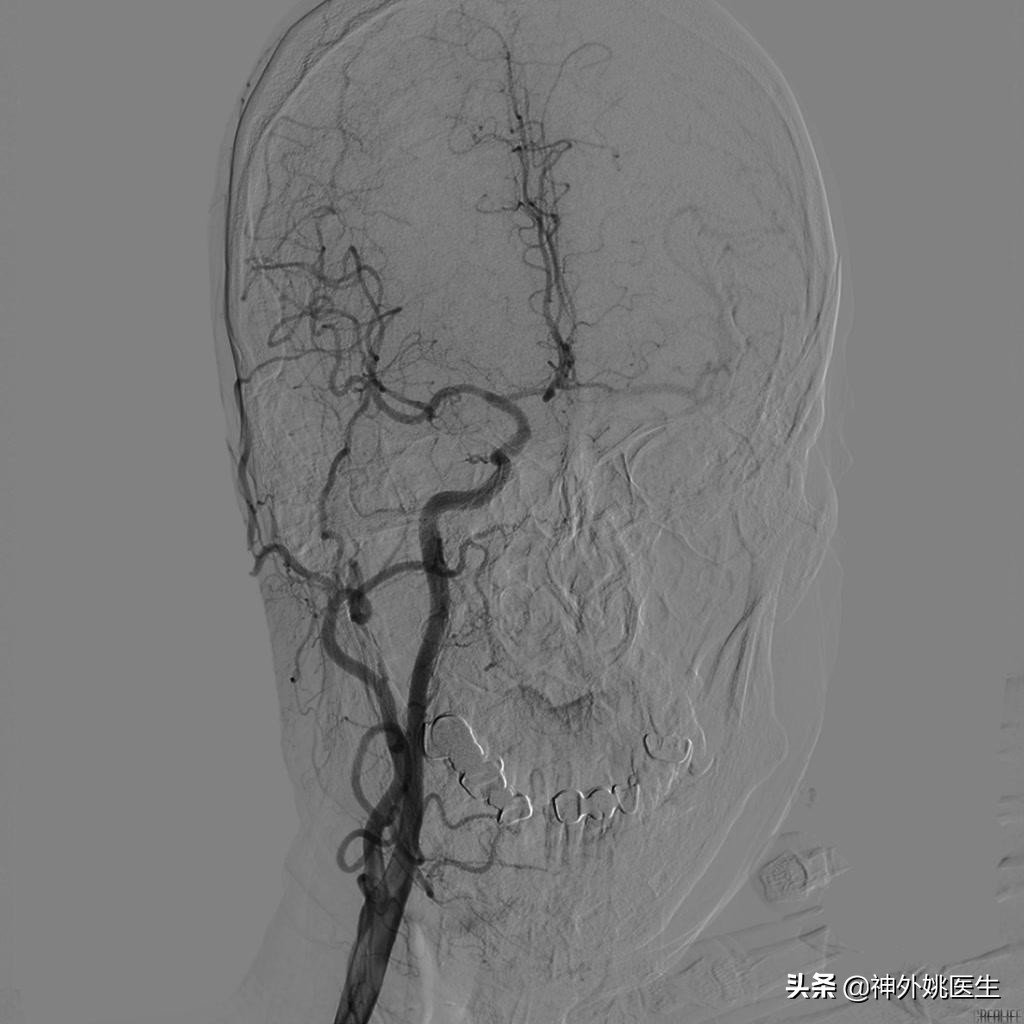

术前DSA检查:(图3-6)

图3 左颈内动脉起始段重度狭窄。

图4 右颈动脉造影示前交通动脉开放,左侧A2以远显影,通过左侧A1至M1以远亦显影。